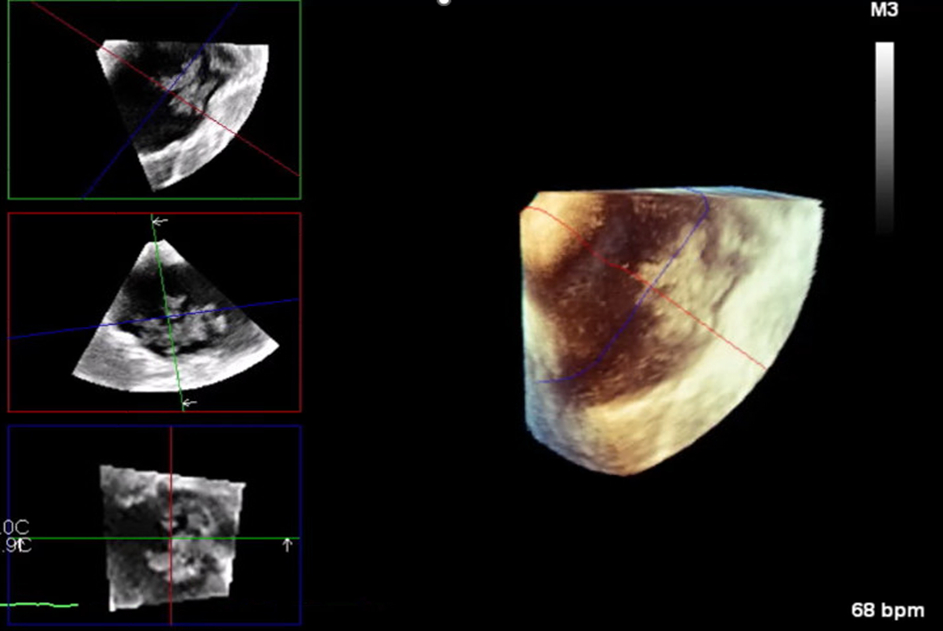

Initial work up